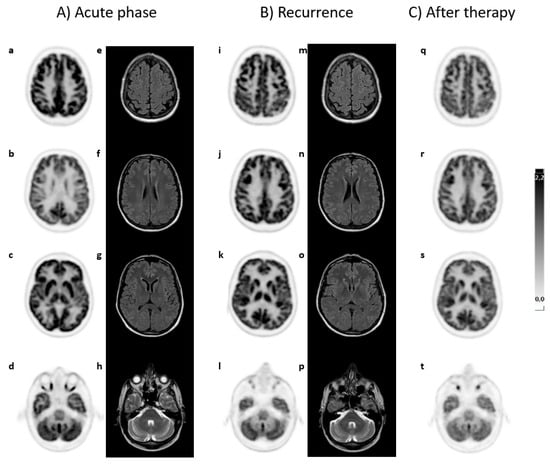

Patient G relapsed six months after the first episode but displayed partial improvement during treatment. A brain PET/CT scan revealed additional hypermetabolic areas in the fronto-parietal and temporal-parietal cortical regions bilaterally, while increased metabolism in the cerebellar vermis persisted. The MRI data remained inconclusive. The patient underwent further cycles of therapy, resulting in partial regression of clinical symptoms. A third brain PET/CT scan indicated that the area of hypermetabolism in the cortical regions continued to persist, although there was a slight reduction in FDG uptake in the cerebellar vermis. The patient is still being monitored. Brain PET/CT and MRI scan for this patient are illustrated in Figure 1.

Figure 1. (A) A 52-year-old male patient (case G) in the acute phase of autoimmune encephalitis (AE) presented with proteinorrhachia, three IgG bands, and later anti-GAD65 antibodies in cerebrospinal fluid (CSF). A brain 18F-FDG PET/CT scan, in transaxial view, indicated increased FDG uptake in the cerebellar vermis (d), while other areas (a–c) exhibited normal uptake. MRI T2/FLAIR (e–h) findings were nonspecific. (B) Six months after the initial acute episode, during which the patient was treated with methylprednisolone and immunoglobulin, a recurrence occurred. A repeat brain 18F-FDG PET/CT showed new areas of hypermetabolism in the fronto-parietal (i,j) and parieto-temporal (k,l) cortical regions bilaterally, as well as persistent hypermetabolism in the cerebellar vermis (m). The MRI results remained nonspecific (n–p). (C) After a second therapy cycle, a new brain 18F-FDG PET/CT scan indicated no significant change in the hypermetabolic cortical areas (q–s), while there was a modest reduction in FDG uptake in the cerebellar vermis (t). No MRI was performed at this time. The patient is still alive and remains under observation.